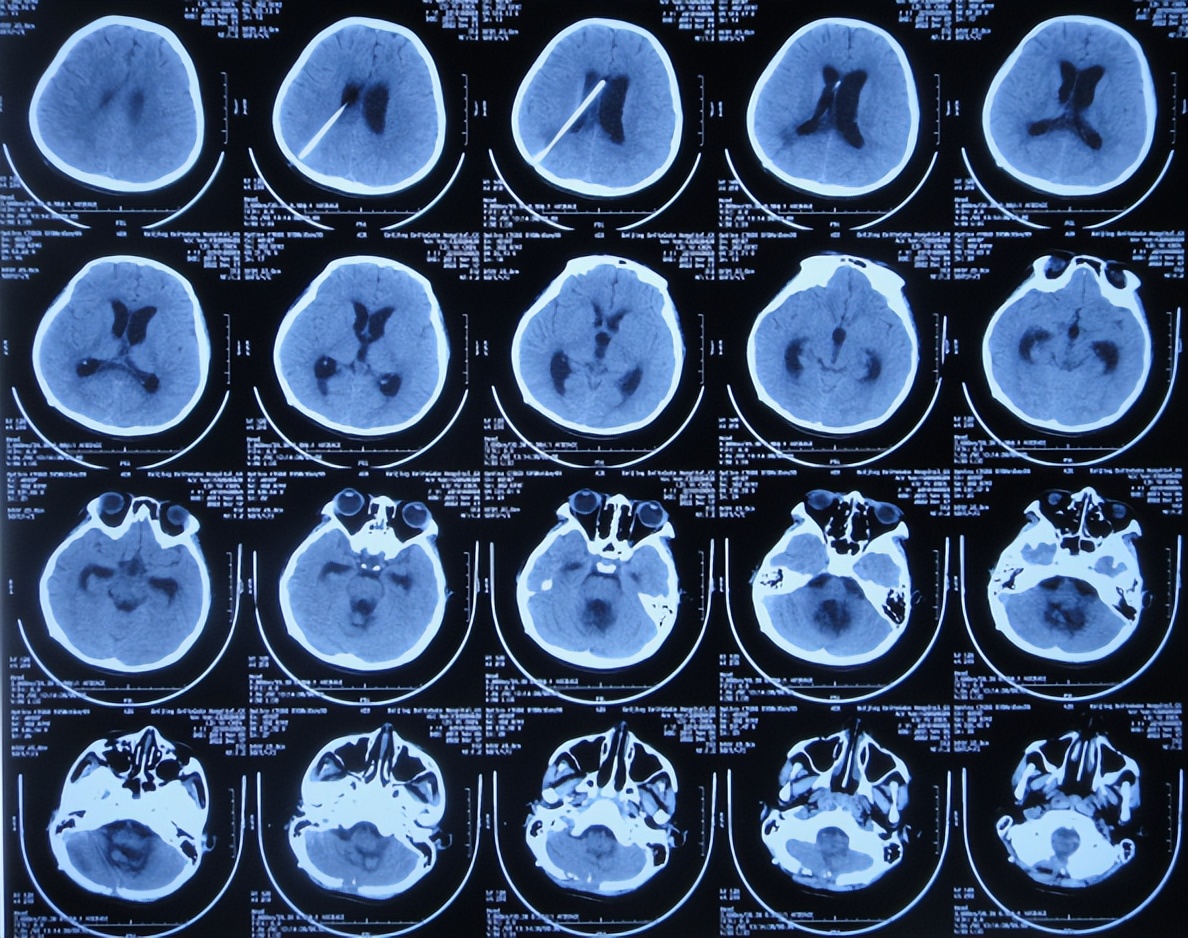

2022年10月16日(小脑出血当天晚上)住入李小勇脑脊液科。入院时:嗜睡,能被叫醒;时有恶心呕吐( 图-2 )。查头颅CT示小脑出血,脑室有扩张( 图-3 );肺部感染( 图-4 )。

图-3: 入院时颅脑CT晚上8点

进一步检查颅脑血管造影( 图-6 )和颅脑核磁增强( 图-7 )示延髓偏后方占位伴延髓损伤,考虑中线胶质瘤伴出血可能性大。

但脑室腹壁外引流术后2天即2022年10月19日,患儿症状并未明显减轻,查颅脑核磁示脑室有缩小( 图-8 ),计划明日进行脑瘤切除术。

2022年10月30日(住院治疗14天),头痛加重,查颅脑CT示脑室又有扩张( 图-12 );肺部感染( 图-13 )。

图-12: 2022年10月30日颅脑CT

2022年12月12日(住院治疗57天),颅脑CT示脑室引流术后状态( 图-15 ),给予夹闭引流管。

但夹闭5天后即2022年12月17日,患儿出现不适,查颅脑CT示脑室有扩张( 图-16 ),打开引流管。

2022年12月20日(住院治疗65天),查头颅CT示脑室缩小( 图-17 ),肺部CT示感染好转( 图-18 )。

图-17: 2022年12月20日颅脑CT

2023年1月9日(住院治疗85天即脑胶质瘤切除术后81天)出院,出院时:意识清楚,头痛恶心完全消失,自己走路不稳( 图-19 );出院时肺部感染变好、颅脑CT示无异常( 图-20 )。

图-20: 出院时颅脑CT